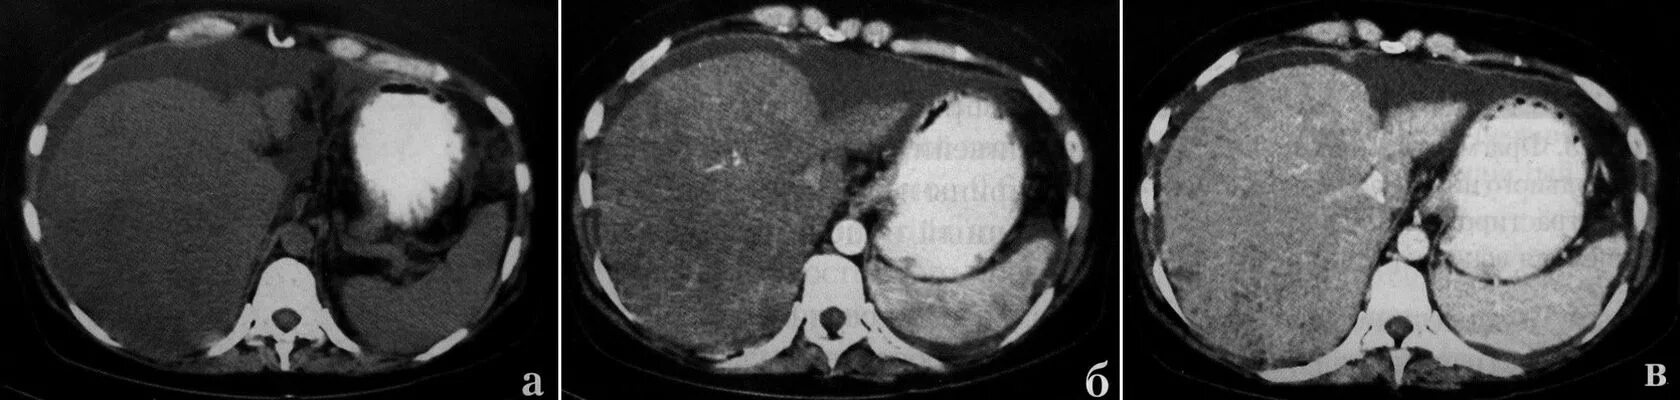

Образования печени кт